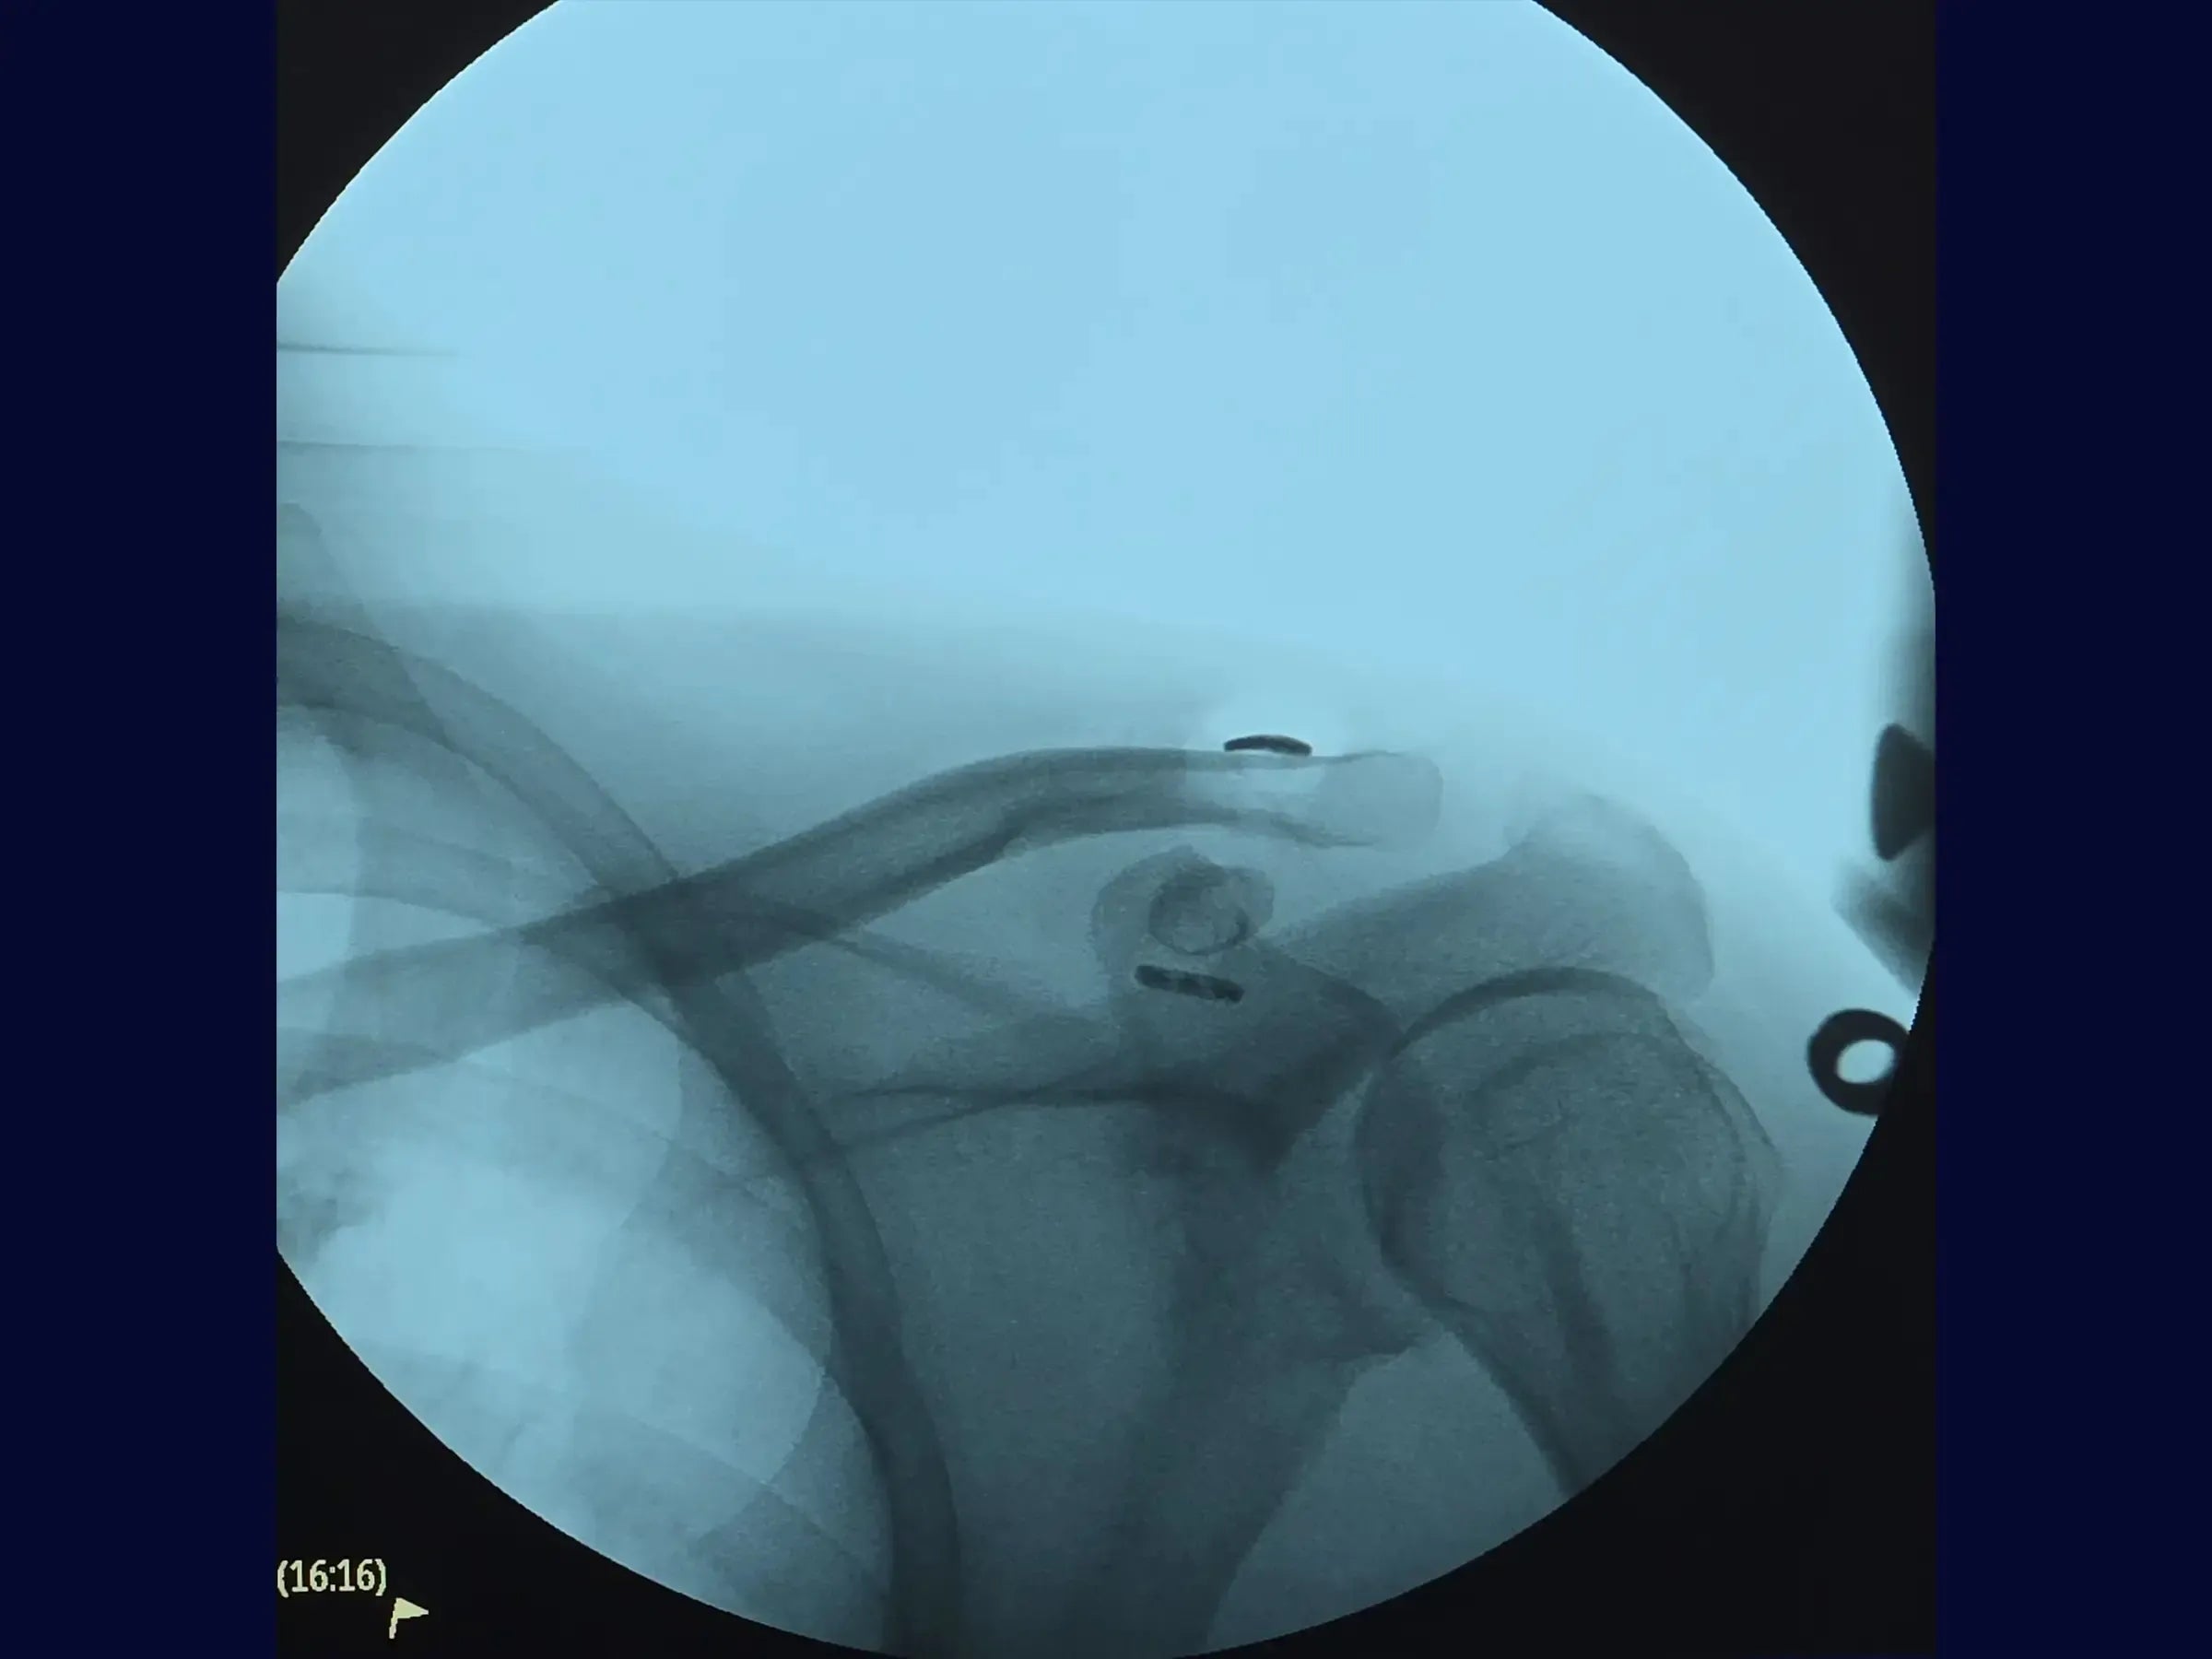

- Evaluación radiográfica precisa: metodología para identificar la base del proceso coracoides utilizando imágenes anteroposteriores (AP) y apicales (axilares) para planificar la inserción del dispositivo.

- Creación de Túneles Óseos Estratégicos: Posicionamiento del túnel en la clavícula en el tercio medio anterior, próximo a la base de la coracoides, y en la apófisis coracoides lo más cerca posible de la base, para evitar el desplazamiento anterior de la clavícula y el fracaso postoperatorio.

- Inserción y ajuste del dispositivo TightRope: Procedimiento secuencial de paso del TightRope a través de los orificios de la clavícula y la coracoides, con tracción alterna de los alambres para reducir y fijar la luxación.